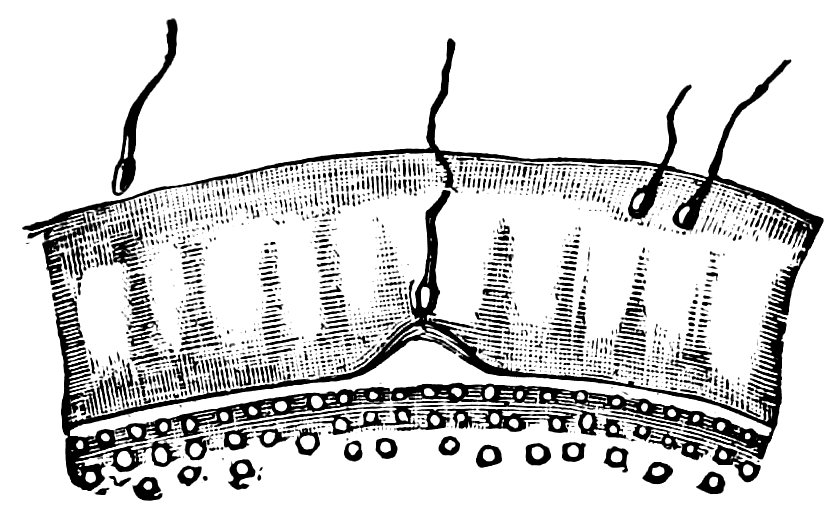

10At the time of puberty the infantile uterus undergoes changes affecting both its external form and the shape of its interior cavity. The body of the uterus enlarges to the size characteristic of sexual maturity, and its mucous membrane becomes the seat of periodic changes. This waxing and waning growth and transformation of the uterine mucous membrane continues throughout the period of menstrual activity, the most superficial layers of the membrane being shed during menstruation, a process followed by regeneration, which is itself succeeded by the premenstrual thickening. When conception occurs, still more extensive changes ensue, the fertilized ovum becoming imbedded in the uterine mucous membrane, and the pregnant uterus, in shape and structure and in the respective relations of the body and neck of the organ, in the increasing distension of its veins and the increasing size of its nerves, becoming adapted to the important functions it has now to fulfil. When these have been fulfilled, and, parturition having taken place, the uterus is empty once more, the organ again adapts itself to altered circumstances by the process of involution. Later, in the climacteric period, a slow regressive process occurs, the outward manifestation of which is the cessation of the menstrual flow, characterized anatomically by atrophy of the muscular tissue of the uterus and of its vascular apparatus, by the dessication of its mucous membrane, by obliteration of the lumen of the uterine cavity, and ultimately by senile degeneration and atrophy of the now entirely functionless organ, so that it becomes an insignificant, cicatrized, solid body.

To the above general sketch, which has been based on the synoptical description of Chrobak von Rosthorn, must be added a more detailed account of the innervation of the ovaries, this branch of the subject being of especial importance. The nerves of the ovary are derived from the sympathetic system, in part from the spermatic ganglion, in part from the second renal ganglion, and in part from the superior mesenteric plexus. The nerves of 13the ovary are for the most part vascular nerves, which unite before entering the ovary to form the ovarian plexus, and then pass into the hilum with the vessels, envelop the vessels of the medullary layer, and thence pass to the follicular region; exceedingly numerous, they form a close-meshed network, surrounding all the vessels up to the finest capillary ramifications; those fibres which terminate in the capillary walls and those also which reach the follicles are regarded by Riese as sensory. The great trunks of the uterine nerves are transversely disposed in relation to the great lateral vessels of the uterus, and passing inward toward the mucous membrane they break up into pencils of filaments; the uterine nerves proper are distributed for the most part to the muscular substance. In the Fallopian tubes, the nerves form arches around the lumen of the tube; some fibres also pass to the longitudinal folds of the mucous membrane.